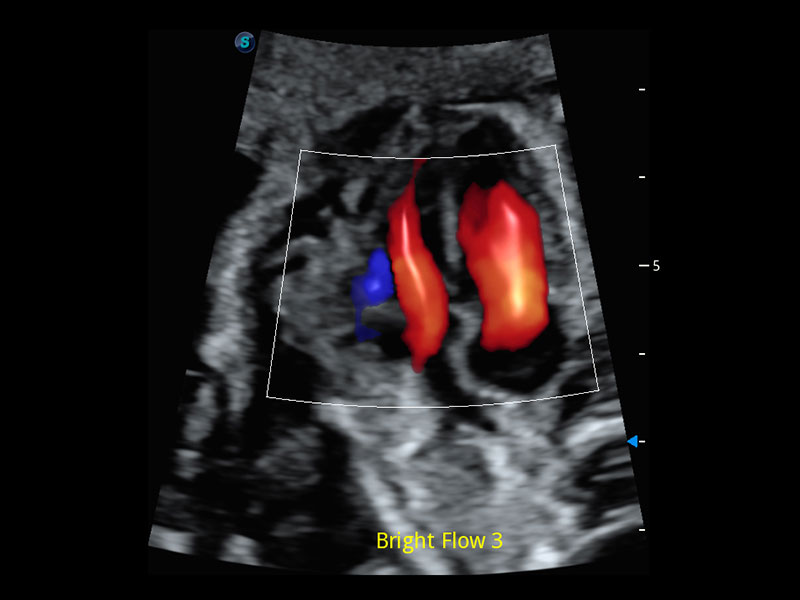

4D HyCoSy mit SPI

Die farbkodierte Hysterosalpingo-Kontrastsonografie (HyCoSy) ist eine proprietäre Funktion auf P60 Exp, die die Ankunftszeit von Kontrastmitteln in verschiedenen Teilen der Gebärmutter, der Eileiter und der Eierstöcke klar demonstrieren kann. Dadurch erhalten Kliniker starke und zuversichtliche Beweise, um die Tubenpatenz bei subfertilen Frauen zu untersuchen.

• Eileiter mit 4D HyCoSy

• Eileiter mit 4D HyCoSy mit SPI